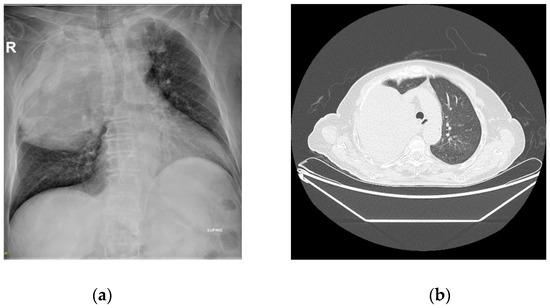

A Case Report of Doege–Potter Syndrome: A Rare Cause of Hypoglycemia in a Patient without Diabetes

Hypoglycemia in patients without diabetes is a diagnostic challenge for the endocrinologist. Sometimes it is related to rare causes such as Doege–Potter Syndrome (DPS). DPS is caused by an abnormal insulin-like grow factor 2(IGF-2) that retains part of the E domain during the [...] Read more.

Hypoglycemia in patients without diabetes is a diagnostic challenge for the endocrinologist. Sometimes it is related to rare causes such as Doege–Potter Syndrome (DPS). DPS is caused by an abnormal insulin-like grow factor 2(IGF-2) that retains part of the E domain during the production process, resulting in a longer peptide called “big-IGF-2”. We present a case report of DPS with emphasis on the diagnosis and especially on the difficulties in interpreting the biochemical findings. An elderly patient with an intrathoracic neoplasm and hypoglycemia underwent various tests: insulin autoantibodies and fasting test were both negative. She had low values of IGF-1 and normal values of IGF-2 that apparently excludes a diagnosis of DPS. The evaluation of the IGF-2/IGF-1 ratio is the most important test because a ratio >10 is widely considered to be indicative of non-islet cell tumor hypoglycemia (NICTH). Glucose infusion and steroid therapy were used to control the hypoglycemia, but the definitive treatment was surgery, which almost immediately reversed the hypoglycemia. The differential diagnosis of hypoglycemia should include rare causes such as DPS, and the IGF-2/IGF-1 ratio is a useful tool. Full article

Figure 1